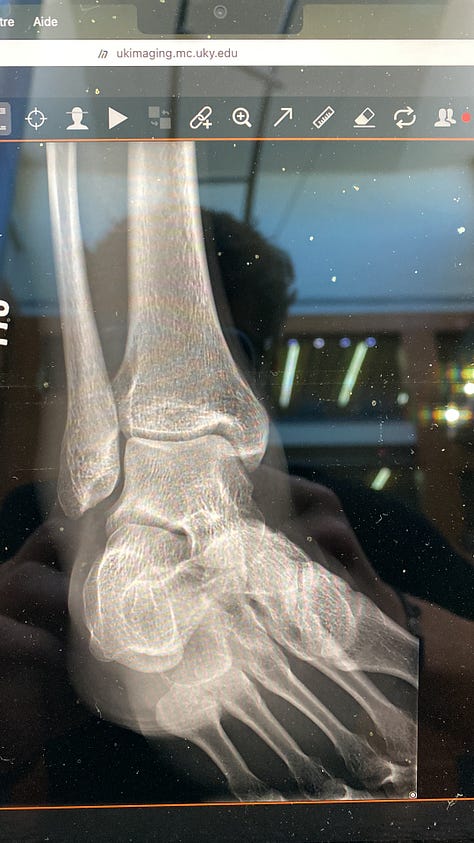

1. La blessure

Lors d’un entraînement pour un petit tournoi de foot, un copain a tiré dans ma cheville au lieu de la balle sans faire exprès, ça a bloqué ma cheville et elle s’est ensuite retournée. Le choc a fait gonfler toute la cheville, en quelques minutes elle est devenue grosse comme une balle de tennis. Une ambulance est venue pour vérifier que ce n’était pas cassé, heureusement que non ! Si en tombant j’avais tapé ma tête sur le sol, j’aurais dû obligatoirement prendre une ambulance pour aller faire un point avec un docteur et deviner le prix de l’ambulance aux États-Unis… 12000€ pour 4 min de route car l’hôpital se situe juste à côté. Un policier m’a même proposé de m’y emmener. Le système médicale est plus simple en France, ce n’est pas comparable.

Voici quelques photos de ma blessure le jour meme, et deux jours après :

J’ai dû marcher avec des béquilles pendant 2 jours et j’ai pu reprendre la marche très lentement et en boitant dès le troisième jour. Après une bonne semaine, j’ai pu reprendre le vélo en faisant attention aux chocs et après trois semaines, j’ai commencé à faire des exercices pour renforcer ma cheville. J’ai repris la course à pied très doucement après un peu plus de 3 semaines et je cours régulièrement pour m’assurer que la cheville se renforce. Une sacrée histoire, mais je suis content que ça n’ait pas été pire ! Pas de foot prévu avant un certain temps…